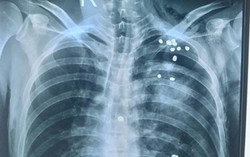

Tuyên Quang: Thêm 1 bệnh nhân bị 20 viên đạn găm khắp lồng ngực

Phòng & chữa bệnh 16:07 23/05/2016Các bác sĩ Bệnh viện (BV) Đa khoa Tuyên Quang vừa thực hiện phẫu thuật lấy 20 viên đạn ra khỏi lồng ngực thành công cho một bệnh nhân. Đây là trường hợp thứ 2 tại Tuyên Quang trong vòng chưa đầy 1 tháng qua phải mổ cấp cứu vì dính đạn